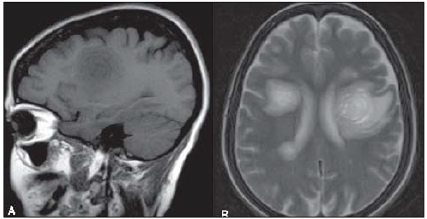

Avalie o seguinte achado radiográfico de uma ressonância magnética, plano sagital ponderada em T1 (A) e axial

ponderada em T2 (B).